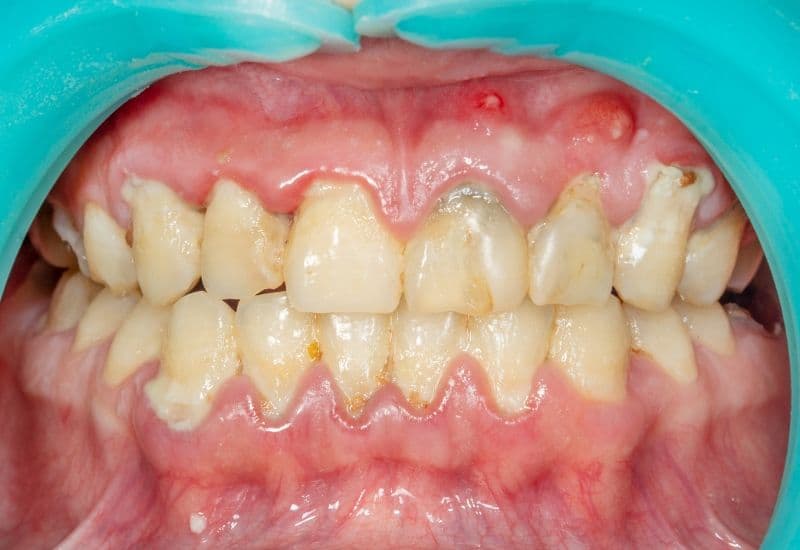

– Mất thẩm mỹ: Cao răng thường có màu vàng hoặc nâu, làm giảm tính thẩm mỹ của nụ cười và có thể ảnh hưởng đến sự tự tin của bạn.

– Viêm nướu và bệnh nha chu: Cao răng tích tụ dưới viền nướu có thể gây kích ứng và viêm nướu. Nếu không được điều trị, tình trạng này có thể tiến triển thành bệnh nha chu, một bệnh lý nha khoa nghiêm trọng, gây tổn thương các mô nâng đỡ răng, có thể dẫn đến lung lay và mất răng.

– Tăng nguy cơ mắc các bệnh lý toàn thân: Nhiều nghiên cứu đã cho thấy mối liên hệ giữa bệnh nha chu do cao răng gây ra với các bệnh lý toàn thân khác như bệnh tim mạch, tiểu đường và các vấn đề về hô hấp.